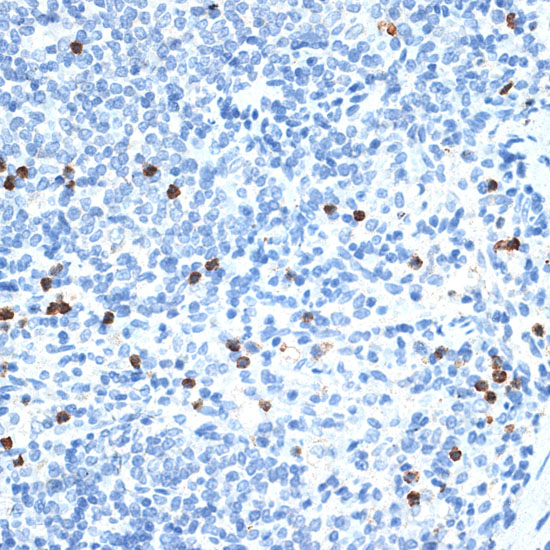

IHC

Ki67 Rabbit pAb